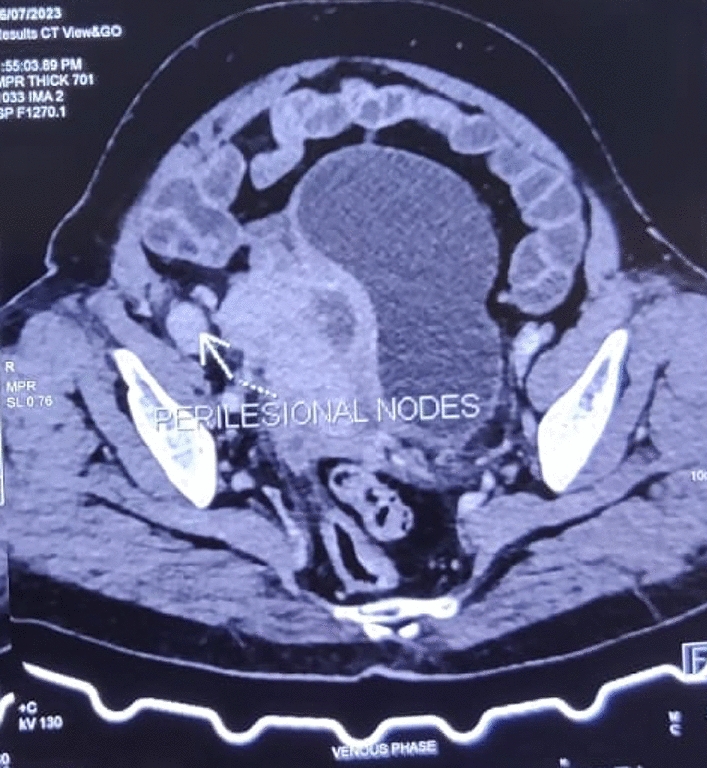

Three female patients with suspected ovarian tumors, based on clinical symptoms, imaging, and elevated CA-125 levels, were reviewed. Each patient underwent staging laparotomy, followed by histopathological examination of the resected masses. Surgical findings, including the presence of sulfur granules and Splendore-Hoeppli phenomenon, confirmed actinomycotic infection in all cases. Post-surgical treatment included prolonged antibiotic regimens tailored to each case.

Histopathology revealed that all patients had extensive actinomycotic infection, marked by inflammatory and fibrotic changes. Notably, none of the patients had a history of IUD use, which is atypical for pelvic actinomycosis cases. Following surgery and antibiotic treatment, all patients achieved full recovery without recurrence, underscoring the effectiveness of this combined approach.